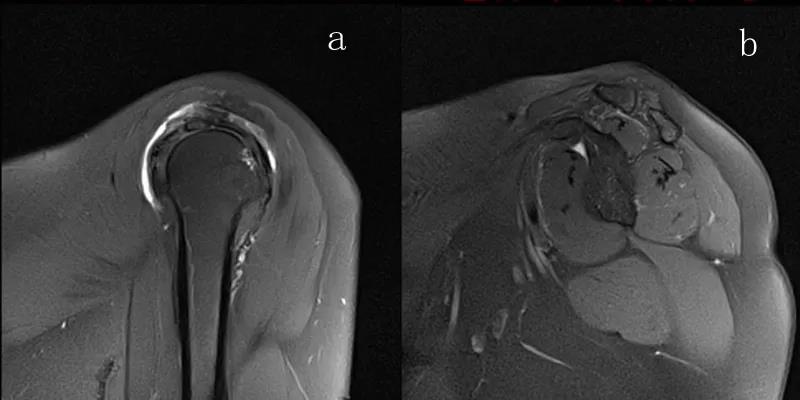

图23 横断位a.正常肩胛下肌;b.肩胛下肌损伤